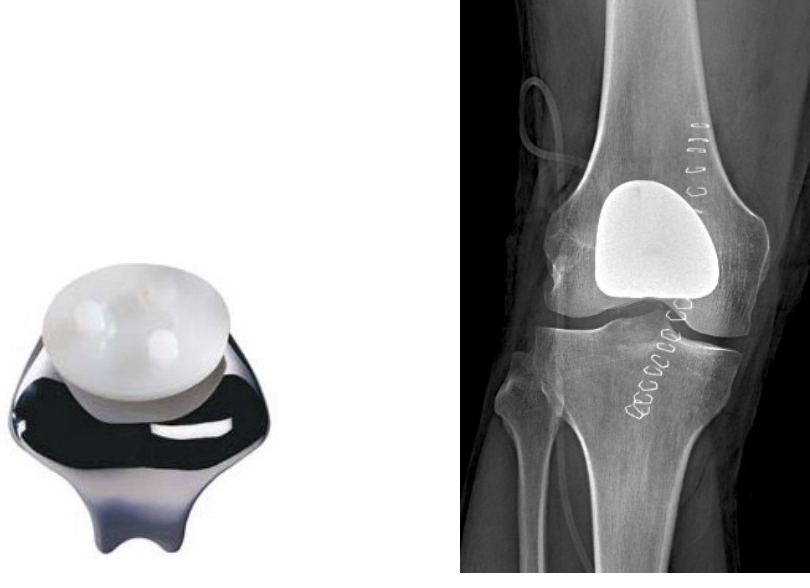

patellofemoral arthroplasty

Patellofemoral replacement

Total knee arthroplasty

3 types: All types REMOVE ACL

CR = Cruciate retraining (PCL retained)

PS = posterior stabilized

RP = rotating platform

rotating platform

special type of PS TKA design to increase surface area to reduce contact stresses

the poly piece can rotate side to side separate from tibia

increased conformity of tibiofemoral articulation

mobile bearing used to diminish any kinematic conflicts